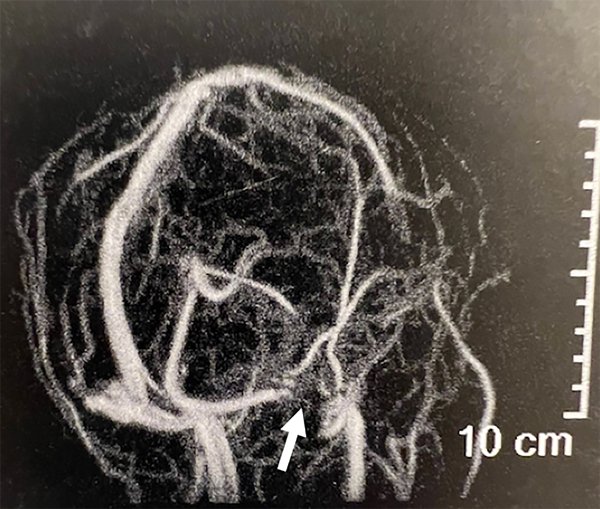

A la paciente se le había ofrecido cirugía de colocación de una válvula de derivación pero la misma rechazó esa opción. Se le realizó una angioRM con tiempos venosos que evidenció la presencia de estenosis de seno transverso derecho (figura 1) por lo que fue derivada a nuestro centro. Le realizamos una angiografía cerebral por punción radial derecha objetivando una estenosis del seno transverso derecho (figura 2A). A la vez, le realizamos un cateterismo venoso por punción femoral derecha y monitoreamos la presión a ambos lados de la estenosis del seno transverso (figura 2B). La presurometría evidenció un gradiente de presión entre el seno longitudinal superior y el seno sigmoideo derecho de 15mm de Hg (figura 2C) por lo que decidimos realizar la angioplastía del seno transverso a nivel de la estenosis.

Figura 1: Angioresonancia en tiempo venoso. La flecha blanca señala la estenosis del seno transverso derecho.